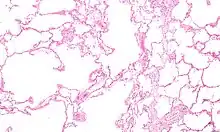

| Section of a lung showing centrilobular emphysema, with enlarged airspaces in the centre of a lobule usually caused by smoking and a major feature of COPD | |